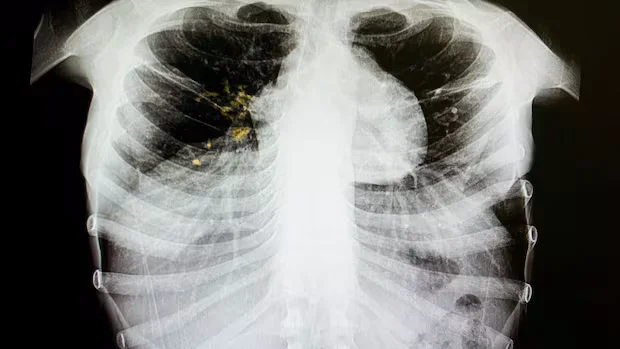

The decision to declare the outbreak was finalized last month after lab results indicating recent local transmission were received. Tuberculosis primarily affects the lungs but can impact other areas of the body. It is an infectious disease that spreads through coughing, sneezing, or spitting from an infected person.